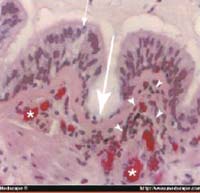

Figura 1. Lesiones histológicas en epitelio bronquial por infección viral: congestión vascular, daño de epitelio, eosinofilia, inflamación.

Encontramos que la etiología viral es la causa más frecuente de infección respiratoria inferior en los niños lactantes y, por lo tanto, el empleo indiscriminado de antibióticos no es prudente. Durante épocas estacionales no usuales como ocurrió en julio 2004 se pueden presentar picos epidémicos por diferentes virus, y el estudio mostró agentes etiológicos diferentes al VSR, los cuales por su agresividad pueden ocasionar el incremento de la mortalidad en el lactante menor El método más rápido y que está a nuestro alcance para la identificación viral, es la detección del antígeno por inmunofluorescencia en el moco de exudado laringotraqueal obtenido por tos inducida. La localidad de Suba tiene factores de riesgo ambiental como humedales, polvo de calles sin pavimentar, pólenes de viveros de flores para exportación, fumigación, humo de industrias, clase socioeconómica estrato 2, 3 con hacinamiento lo cual la hace susceptible para la infección viral de los niños. El broncoespasmo recurrente del lactante después de una bronquiolitis se presenta por reinfección viral, especialmente por rinovirus, llevando a una neumopatía recurrente y posteriormente asma en las edades mayores, en un 85% de los niños. Las reinfecciones ocurren por rinovirus, virus sincitial respiratorio, influenza y parainfluenza. En nuestro medio estas infecciones se presentan en los jardines y grupos de escolares en los meses de abril, mayo y octubre, noviembre. Por los cambios climatológicos actuales se presentan epidemias en otras fechas. La respuesta inmunológica del niño lactante menor es diferente a la del adulto ante la infección viral. Algunos muestran niveles altos de Th2 en respuesta al V.S.R con aumento de IL-4, eosinofilia en vía aérea y anticuerpos IgE específicos elevados con una gran respuesta inflamatoria bronquiolar.